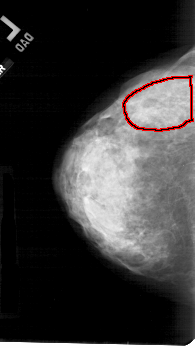

A_1699_1.LEFT_CC

LEFT_CC LINES 5206 PIXELS_PER_LINE 2911 BITS_PER_PIXEL 12 RESOLUTION 43.5 OVERLAY

FILE: A_1699_1.LEFT_CC.OVERLAY

TOTAL_ABNORMALITIES 1

ABNORMALITY 1

LESION_TYPE CALCIFICATION TYPE PLEOMORPHIC DISTRIBUTION SEGMENTAL

ASSESSMENT 4

SUBTLETY 3

PATHOLOGY MALIGNANT

TOTAL_OUTLINES 1

BOUNDARY